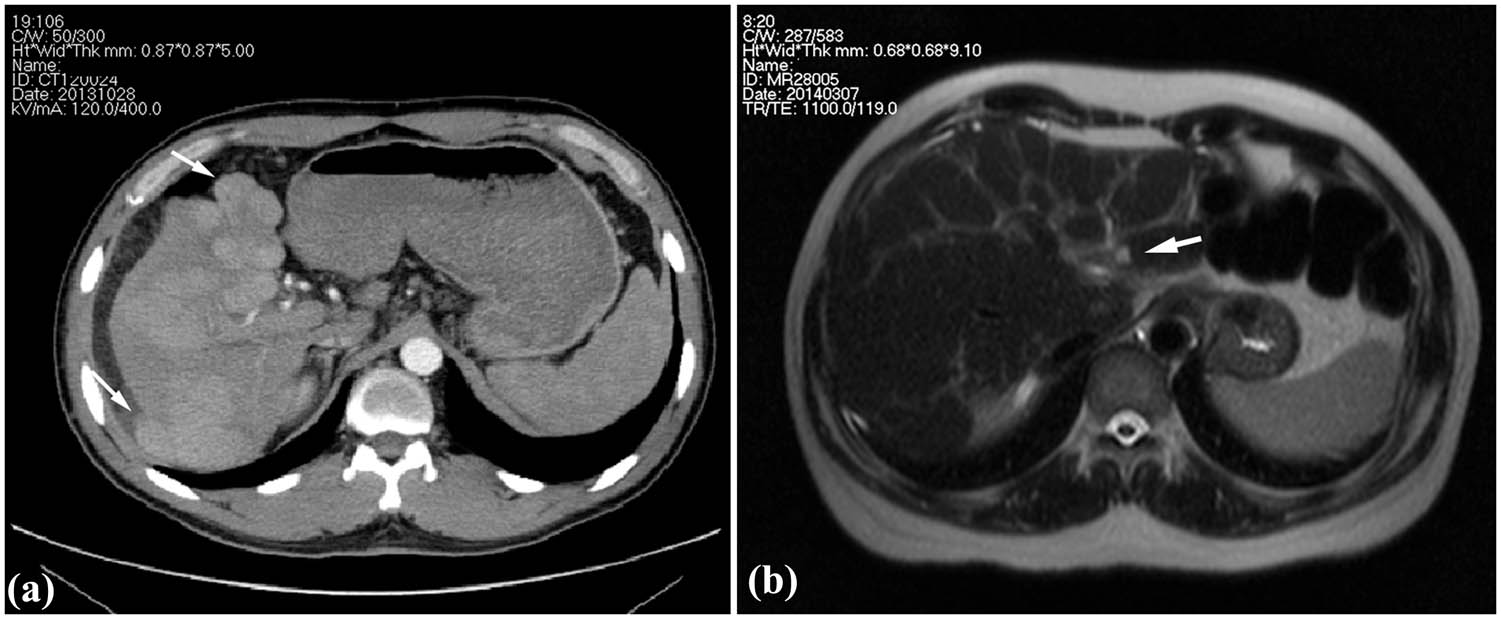

Case 1: A 36-year-old man was admitted to the hospital with chief complaints of abdominal distention, fatigue, and jaundice that persisted for 2 weeks. The patient had a history of exposure to DMF owing to his job at a leather factory 2.5 months before admission (the first 2 months of drying operation and the next 0.5 month of stirring operation). The patient experienced somnolence and was found to be positive for asterixis. The whole-body skin and sclera had turned severely yellow, with petechiae and ecchymosis noted in both lower limbs. The abdominal shifting dullness was positive. The biochemical analysis revealed: alanine aminotransferase (ALT) 589 U/L, aspartate aminotransferase (AST) 559 U/L, total bilirubin (TBIL) 411 µmol/L, direct bilirubin (DBIL) 273.6 µmol/L, prothrombin activity (PTA) 23%, and fibrinogen 0.83 g/L. Results of serological tests for hepatitis virus, cytomegalovirus, and EB virus were negative. Autoimmune antibodies, ceruloplasmin, and anti-hepatic antigens were not detected. No complications of other organ damage were found. Thus, there were indications of acute severe dimethylformamide poisoning, acute liver failure, and hepatic encephalopathy (phase A2). After admission, the patient received anti-hepatic encephalopathy, infusion of albumin and plasma, prothrombin complex, plasma exchange, and other therapies, and after 2 weeks, he gained consciousness. After 123 days of treatment, liver and coagulation functions returned to normal at discharge (the tendency chart can be seen in Figure A1). On the 78th day of admission, according to the enhancement CT, multiple intrahepatic nodules were significantly enlarged, evenly enhanced in the arterial phase (Figure 1a), and isopycnic with peripheral liver tissues in the portal and delayed phases. Malignant lesions could not be excluded [18]; therefore, a percutaneous liver biopsy was conducted on the 83rd day after obtaining informed consent.

Images of clinical cases. (a) Enhancement CT showing the multiple intrahepatic nodules protruded from the liver surface (arrow) in Case 1 and (b) T2WI of MR showing heterogeneous fibrosis and a nodule in the left inner lobe (arrow) in Case 2.

Case 2: A 50-year-old man was admitted to the hospital with chief complaints of abdominal distention, abdominal pain, and poor appetite with yellowing of the skin and sclera that persisted for 1 week. The patient was employed at the local leather factory 5 months before the onset (the first 4 months of drying operation and the next 1 month of coating process). He had a history of exposure to DMF and no alcohol abuse. The shifting dullness was positive. Serological tests for hepatitis virus, cytomegalovirus, and EB virus, autoimmune antibodies and ceruloplasmin were all negative. Biochemical investigations revealed: ALT 321.2 U/L, AST 304.5 U/L, TBIL 231.8 µmol/L, DBIL 127.3 µmol/L, PTA 27%, and fibrinogen 1.06 g/L. The patient was diagnosed with acute severe dimethylformamide poisoning and acute liver failure. Liver protection drugs, infusion of plasma and albumin, and plasma exchange were administered after admission. The symptoms improved, and jaundice faded away, with the PTA gradually recovering. The patient was discharged from the hospital 33 days after admission, returning for re-examination 40 days after discharge. Liver function and coagulation function were normal (the tendency chart can be seen in Supplement Figure 2). Hepatic MR enhancement scan showed reduced liver volume, wavy edge, and an imbalanced proportion of the liver lobe with heterogeneous fibrosis (Figure 1b). Multiple intrahepatic patchy signals, with long T1 signals and slightly long T2 signals, showed enhanced signals after enhanced scan; hence, a percutaneous liver aspiration biopsy was conducted 73 days after the onset.